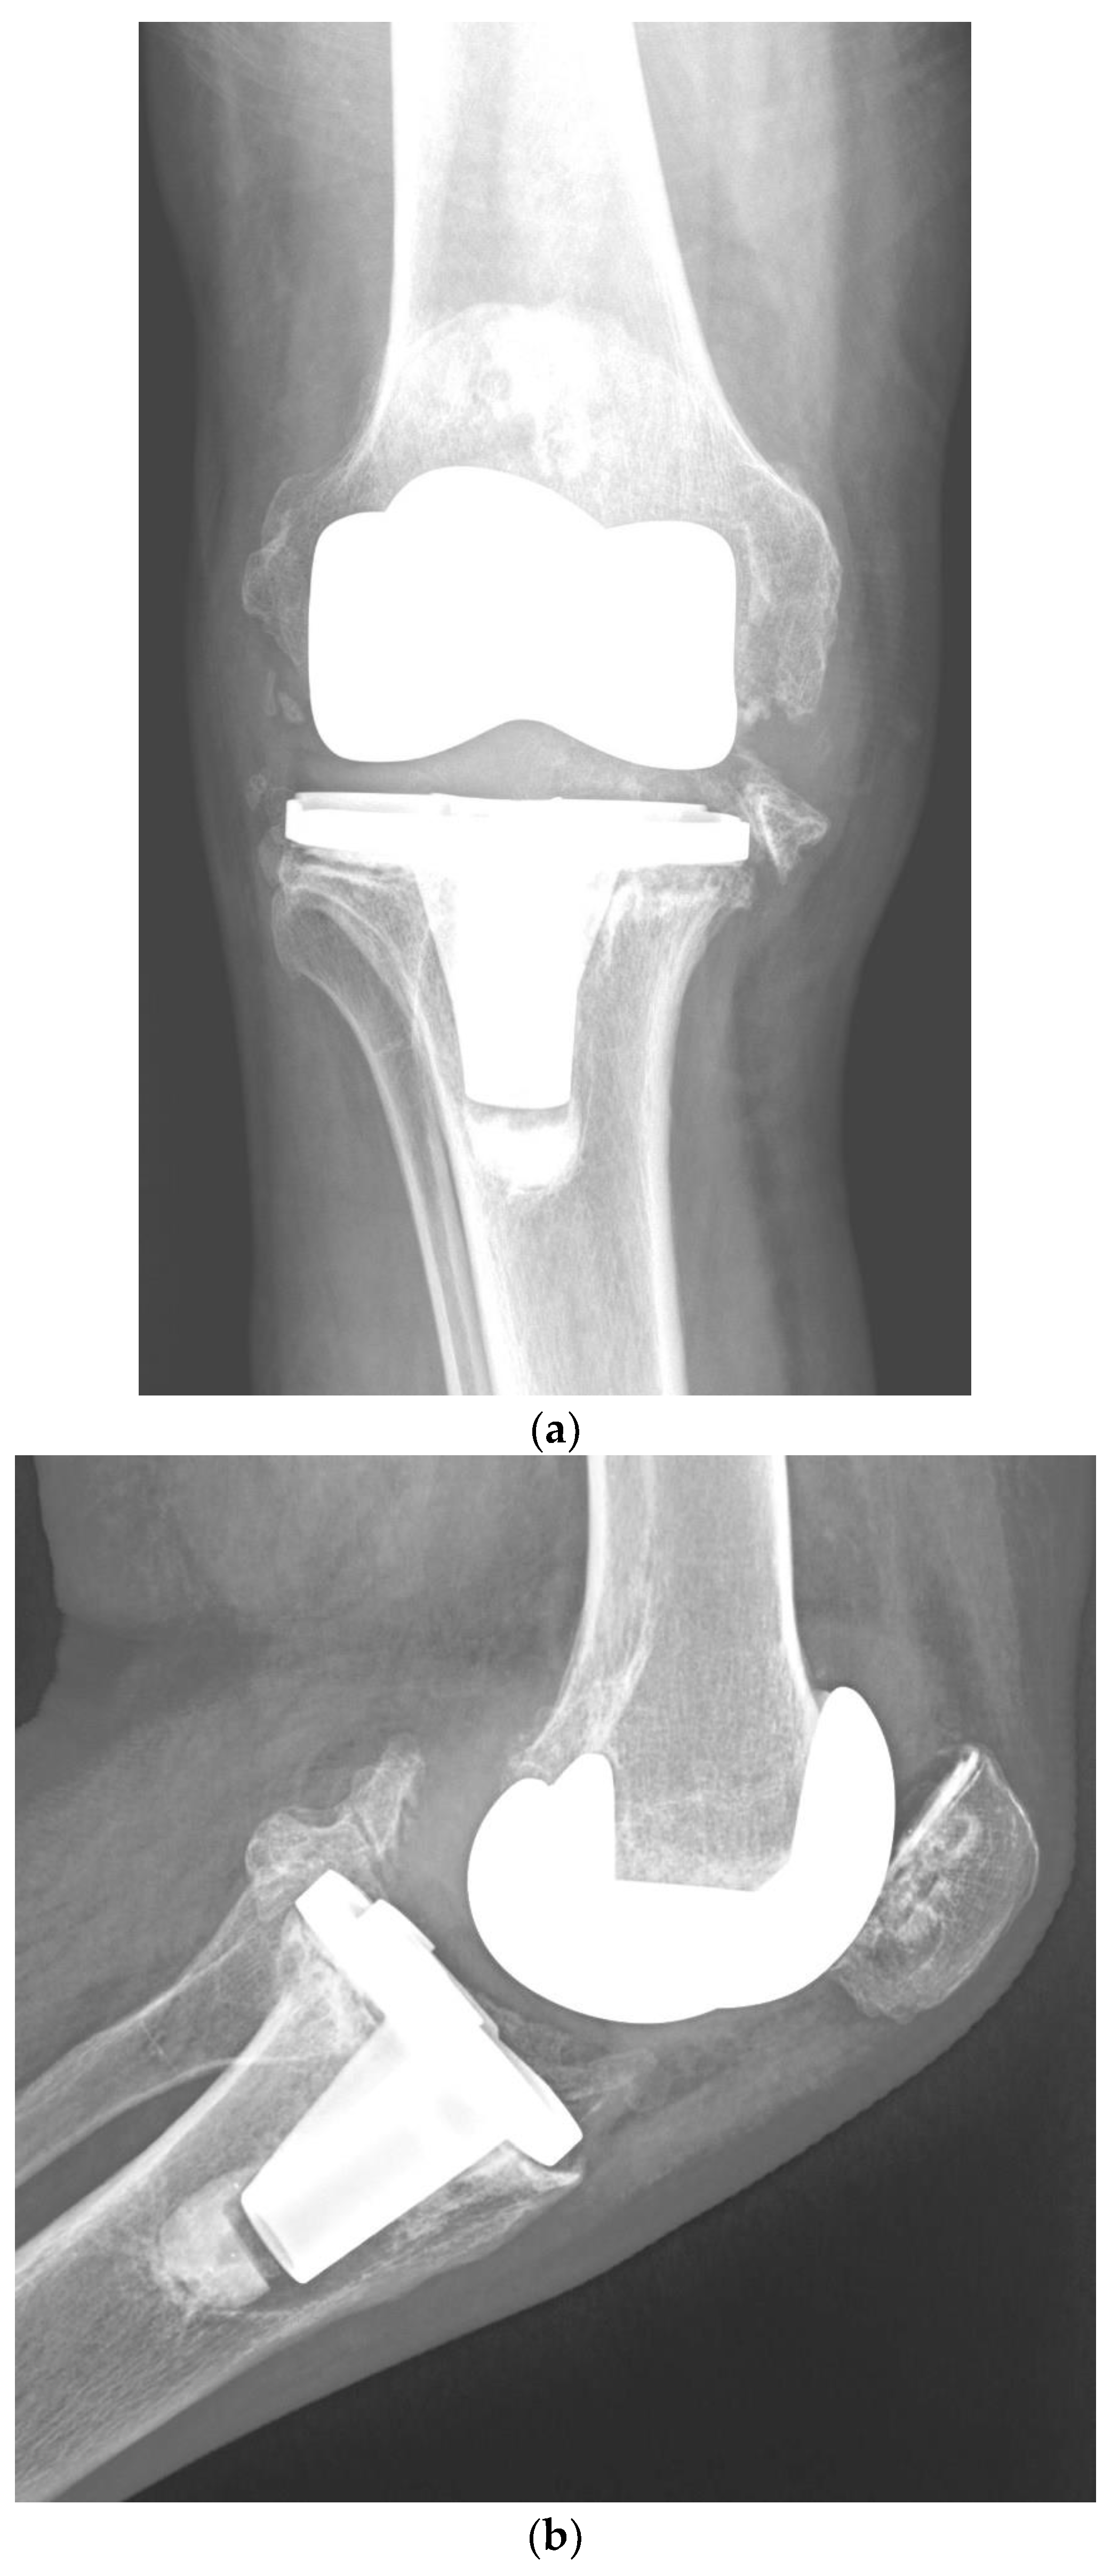

Infected knee joint prosthesis Stock Image C015/1266 Science What Is A Prosthetic Joint Infection — prosthetic joint infections are serious complications of hip and knee arthroplasty and a common cause for revision arthroplasty. — prosthetic joint infection (pji) remains one of the most serious complications of prosthetic joint. — periprosthetic joint infection (pji) is a unique clinical entity, markedly different from infections involving native bones or joints. prosthetic joints are. What Is A Prosthetic Joint Infection.